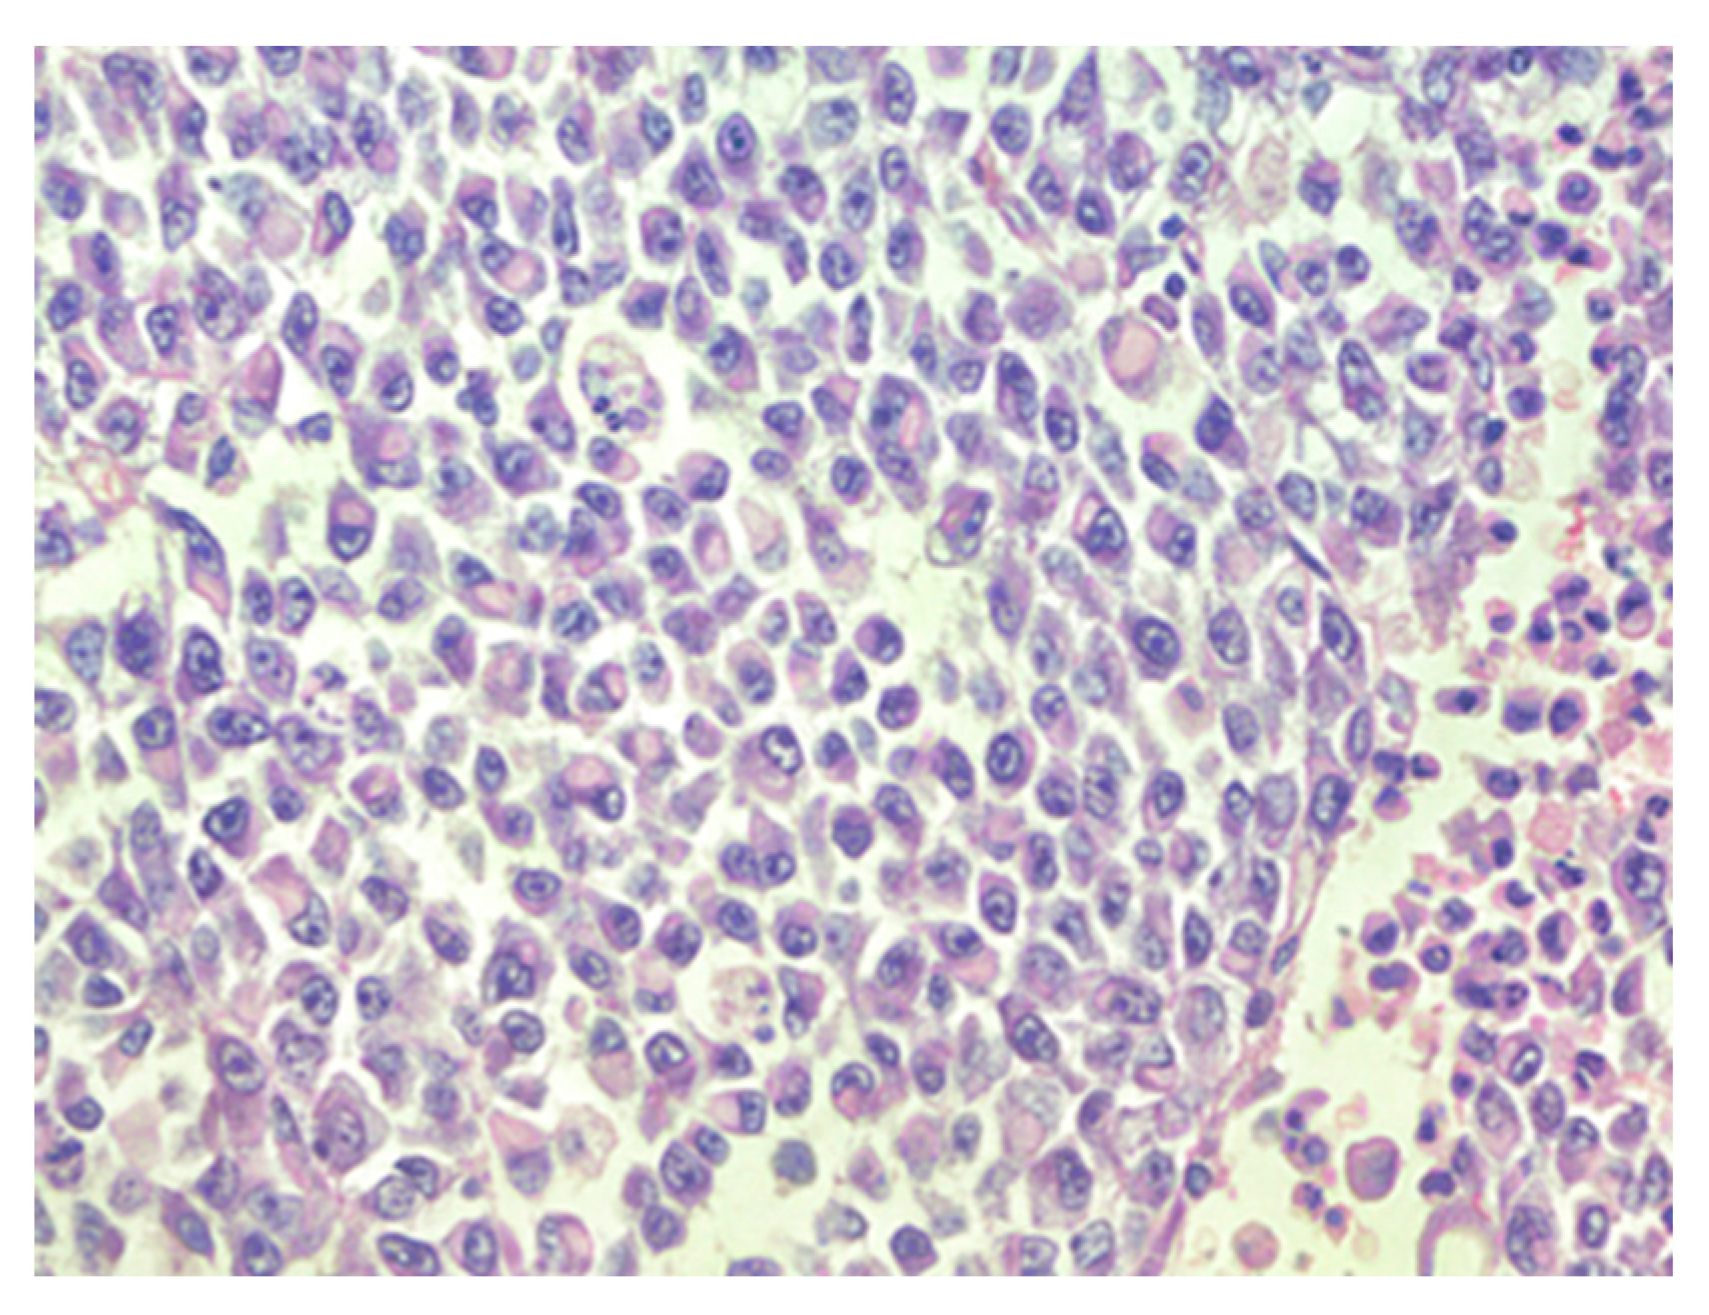

Figure 1.

Densely packed tumor cells and focal hemorrhages in tumor tissue, hematoxylin–eosin, original magnification ×100.